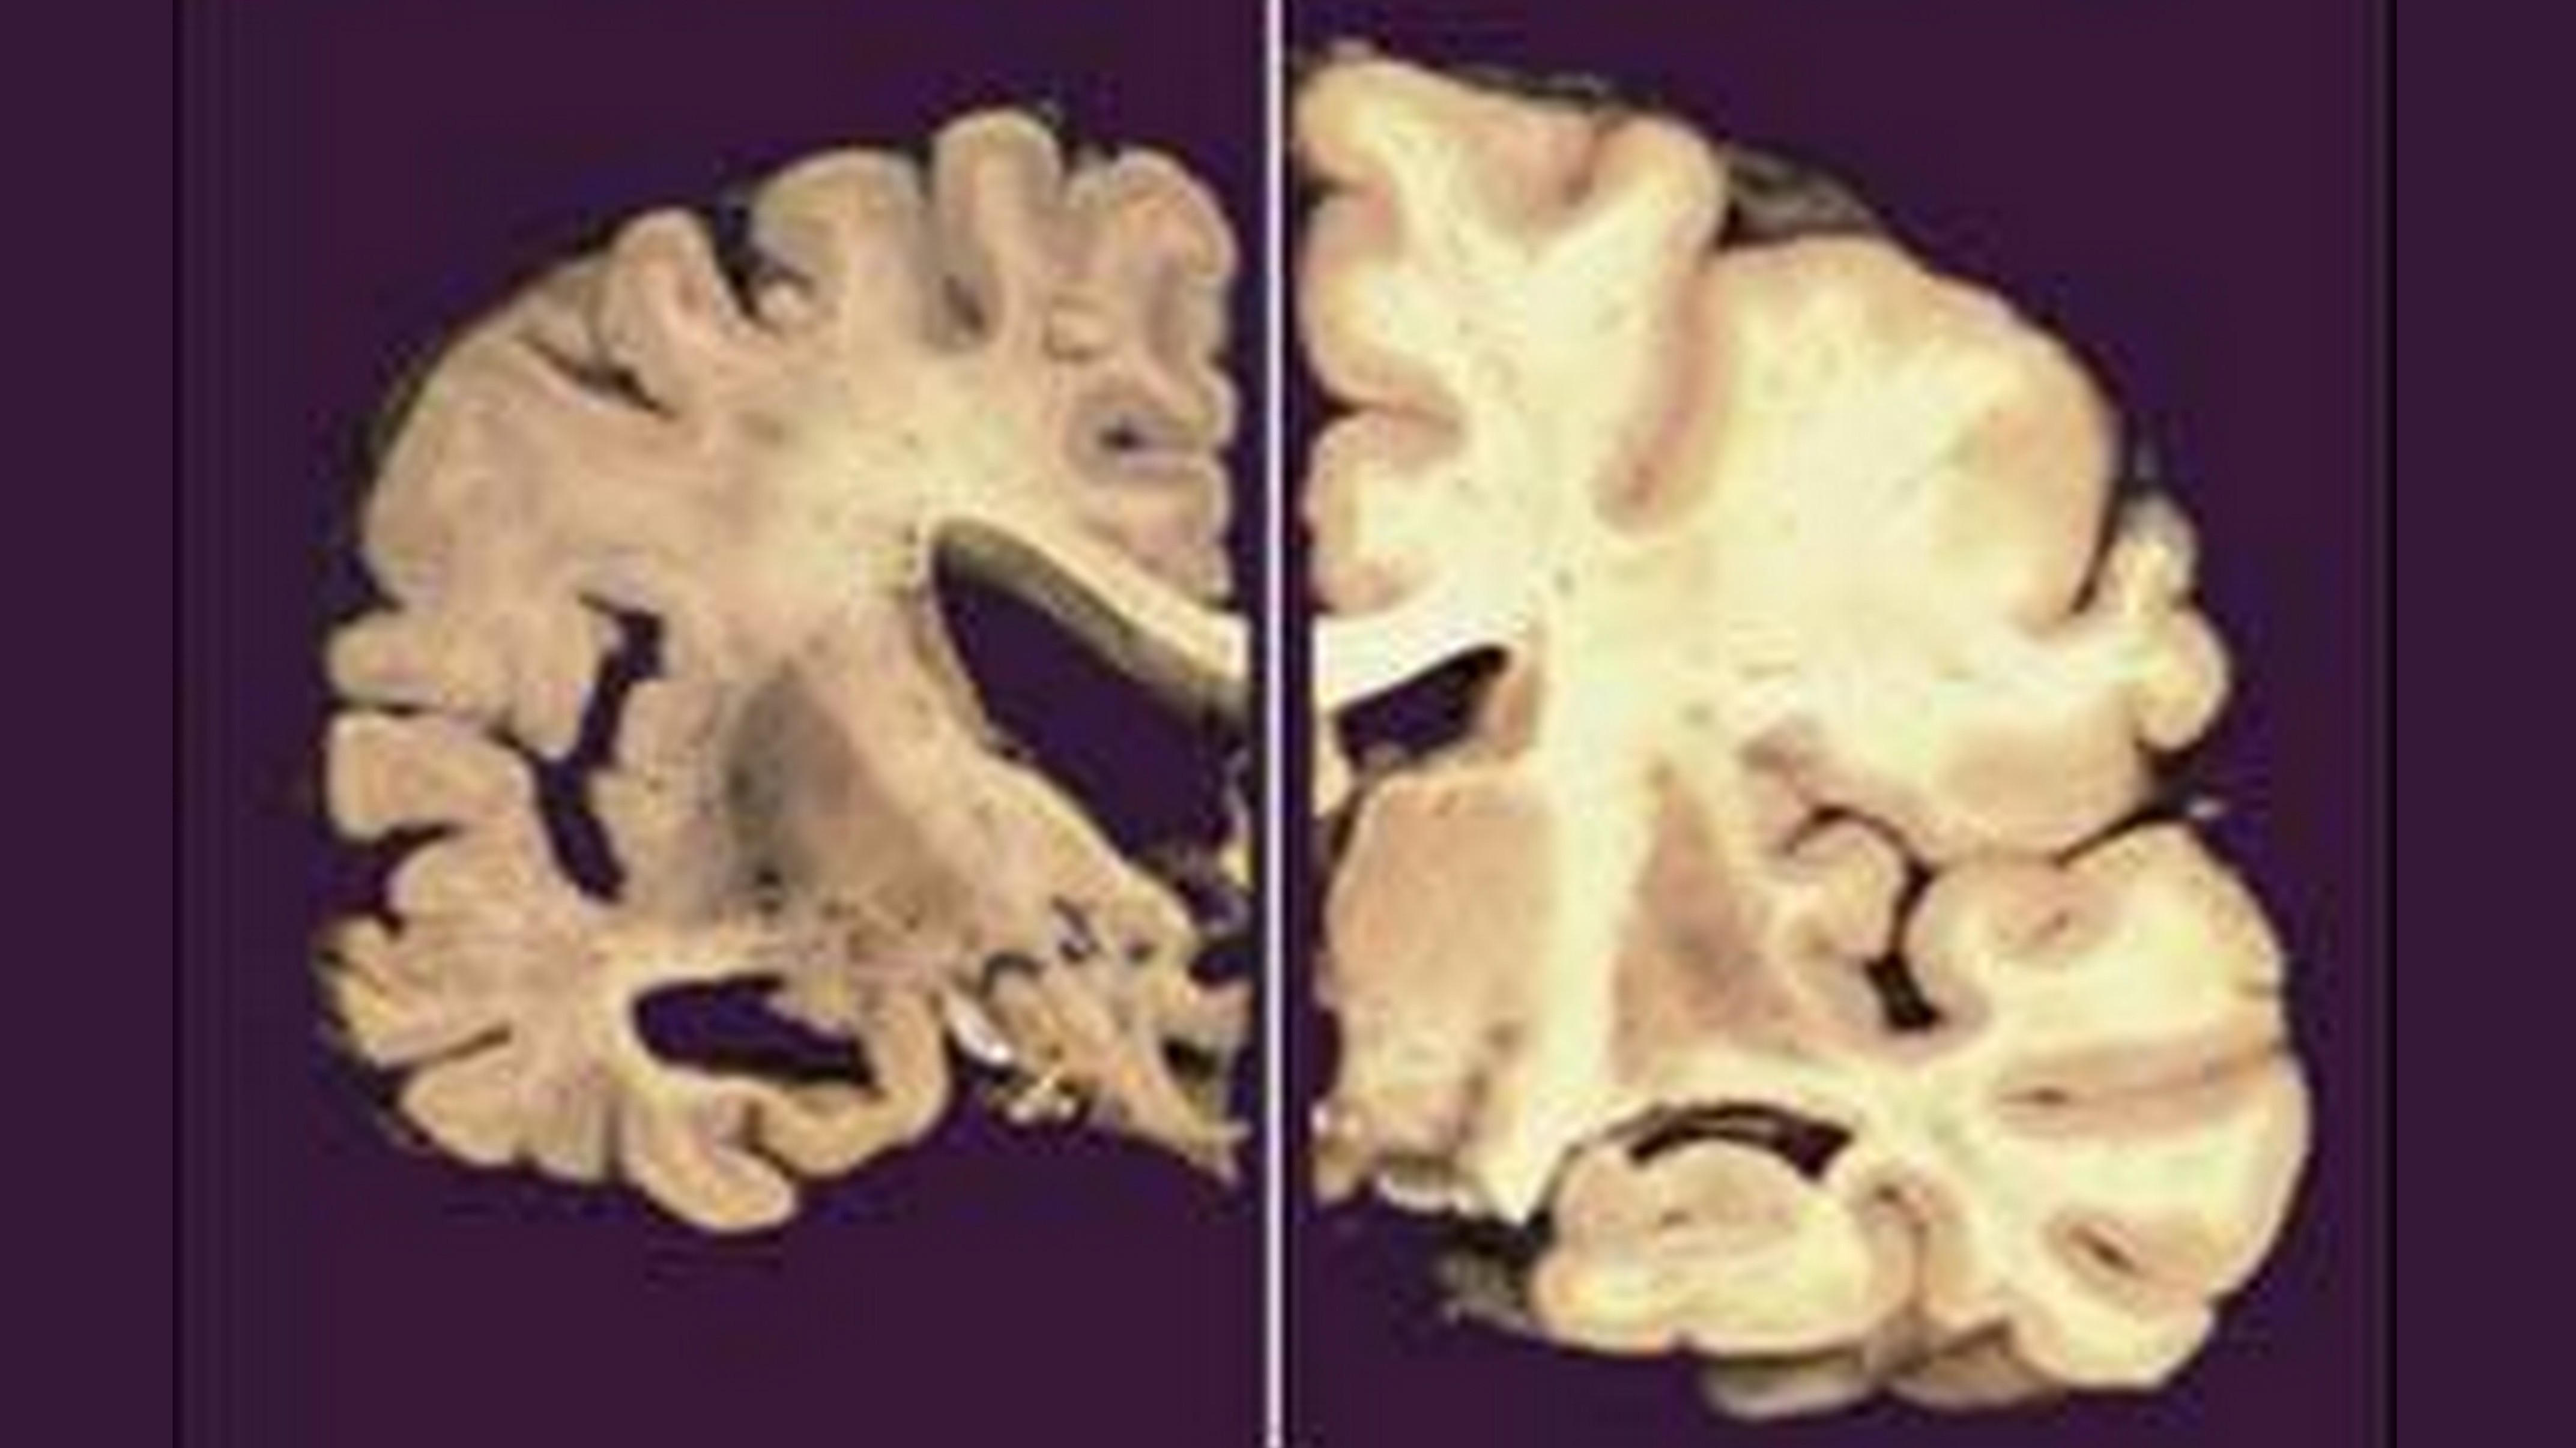

SITA - mozog postihnutý Alzheimerom a zdravý mozog